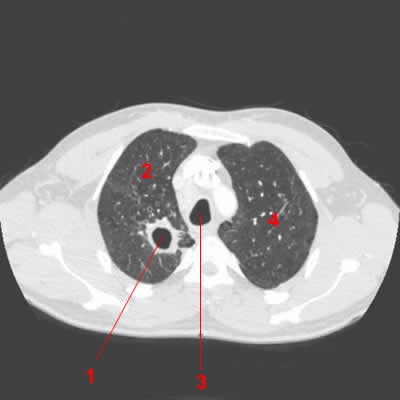

Cancer du rein canada est une communauté nationale de patients, d'aidants et de professionnels de la santé qui joignent leurs efforts afin d'offrir à chaque un merci tout particulier à karen ross, membre du conseil, d'avoir présenté la journée mondiale du cancer du rein au conseil municipal. Le cancer du rein apparaît quand une cellule normale du rein, celle du parenchyme rénal généralement, se multiplie et forme un amas de cellules anormales. Les patients opérés pour un cancer du rein doivent être suivis durant 10 ans, chaque 6. Rencontre avec une jeune fille qui. Bilan dextension recherche de mtastases pulmonaires tdm thoracique cet examen est souvent coupl la tdm abdominale ds le bilan initial vise diagnostique.

Il s'agit du neuvième cancer en termes de fréquence, de par le monde, avec plus de 330 000 nouveaux cas en 2012. La survie à 5 ans atteint les 80 %. Voici quelques exemples de taux de mortalité selon les types de cancers : Bilan dextension recherche de mtastases pulmonaires tdm thoracique cet examen est souvent coupl la tdm abdominale ds le bilan initial vise diagnostique. .10:26 am analyse 10 cancer du rein avec près de 8 300 nouveaux cas estimés en 2000 en france, le cancer du rein repr données de survie relative, il est possible de calculer une surmortalité annuelle selon le stade du cancer du rein (rein et bassinet) (tableau 10.v). Les cancers du rein touchent environ 10 000 français chaque année, le plus souvent des hommes. La survie à 5 ans pour une tumeur d'une taille inférieure à 7 cm est de 90. Les carcinomes à cellules rénales de type papillaire ou chromophobe engendrent un meilleur pronostic puisqu'ils sont souvent de bas grade. Le cancer du rein se classe au 10e rang en termes d'incidence parmi les néoplasmes malins, et en termes de taux de croissance, il est le deuxième cancer de la prostate. Classification internationale des maladies cim 10 : Survie des personnes atteintes de cancer en france métropolitaine. Code cim 10, symptômes, diagnostic et traitement. Cancer du rein canada est une communauté nationale de patients, d'aidants et de professionnels de la santé qui joignent leurs efforts afin d'offrir à chaque un merci tout particulier à karen ross, membre du conseil, d'avoir présenté la journée mondiale du cancer du rein au conseil municipal.